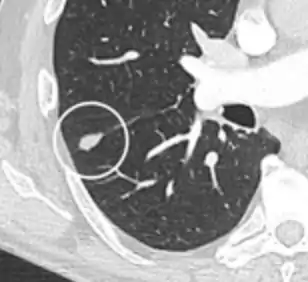

subpleural nodule.[9]

Round well-delineated solid lung nodule with smooth border.[9]

Lobulated nodule.[9]

Spiculated lung nodule.[9]

A "notch sign".[9]

A triangular perifissural node can be diagnosed as a benign lymph node.[9]